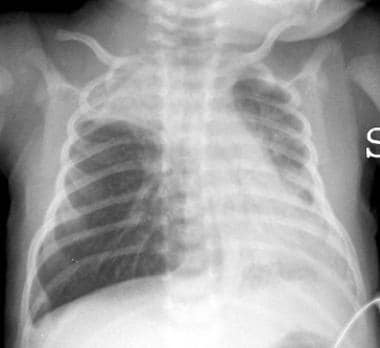

Bronquiolitis es una infección pulmonar que es muy común en niños pequeños y bebés. Regularmente suele causar inflamación y congestión de las pequeñas vías respiratorias es decir los bronquiolos del pulmón. Enfermedad es más común en los niños que los adultos.

Algunas de las complicaciones de la bronquiolitis son los labios o piel azulada, las pausas en la respiración o apnea, deshidratación y bajos niveles de oxígeno.